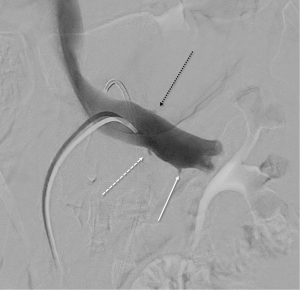

A comparison of DUS (LRV systolic velocity ratios) to CT (vein diameter ratios) demonstrates higher sensitivity and specificity of DUS findings (sensitivity of 80% vs. 69%; specificity of 94% vs. 89%, respectively) (34,36). However, invasive testing is frequently pursued for definitive diagnosis, as therapy could require invasive surgery. Venography with direct pressure measurements (Figure 7) (17), with or without intravascular ultrasound (IVUS), is considered the “gold standard” for diagnosis. However, even studies evaluating these methods utilized cystoscopy to confirm isolated left-sided hematuria (2). An elevated pressure gradient between the LRV and the IVC (≥3 mmHg) is the standard reference point by which venous hypertension is diagnosed (43). However, it should be noted that some patients may be symptomatic with “compensated” NCS, where compensatory flow through collaterals is large enough that only a borderline renocaval pressure gradient exists (2).